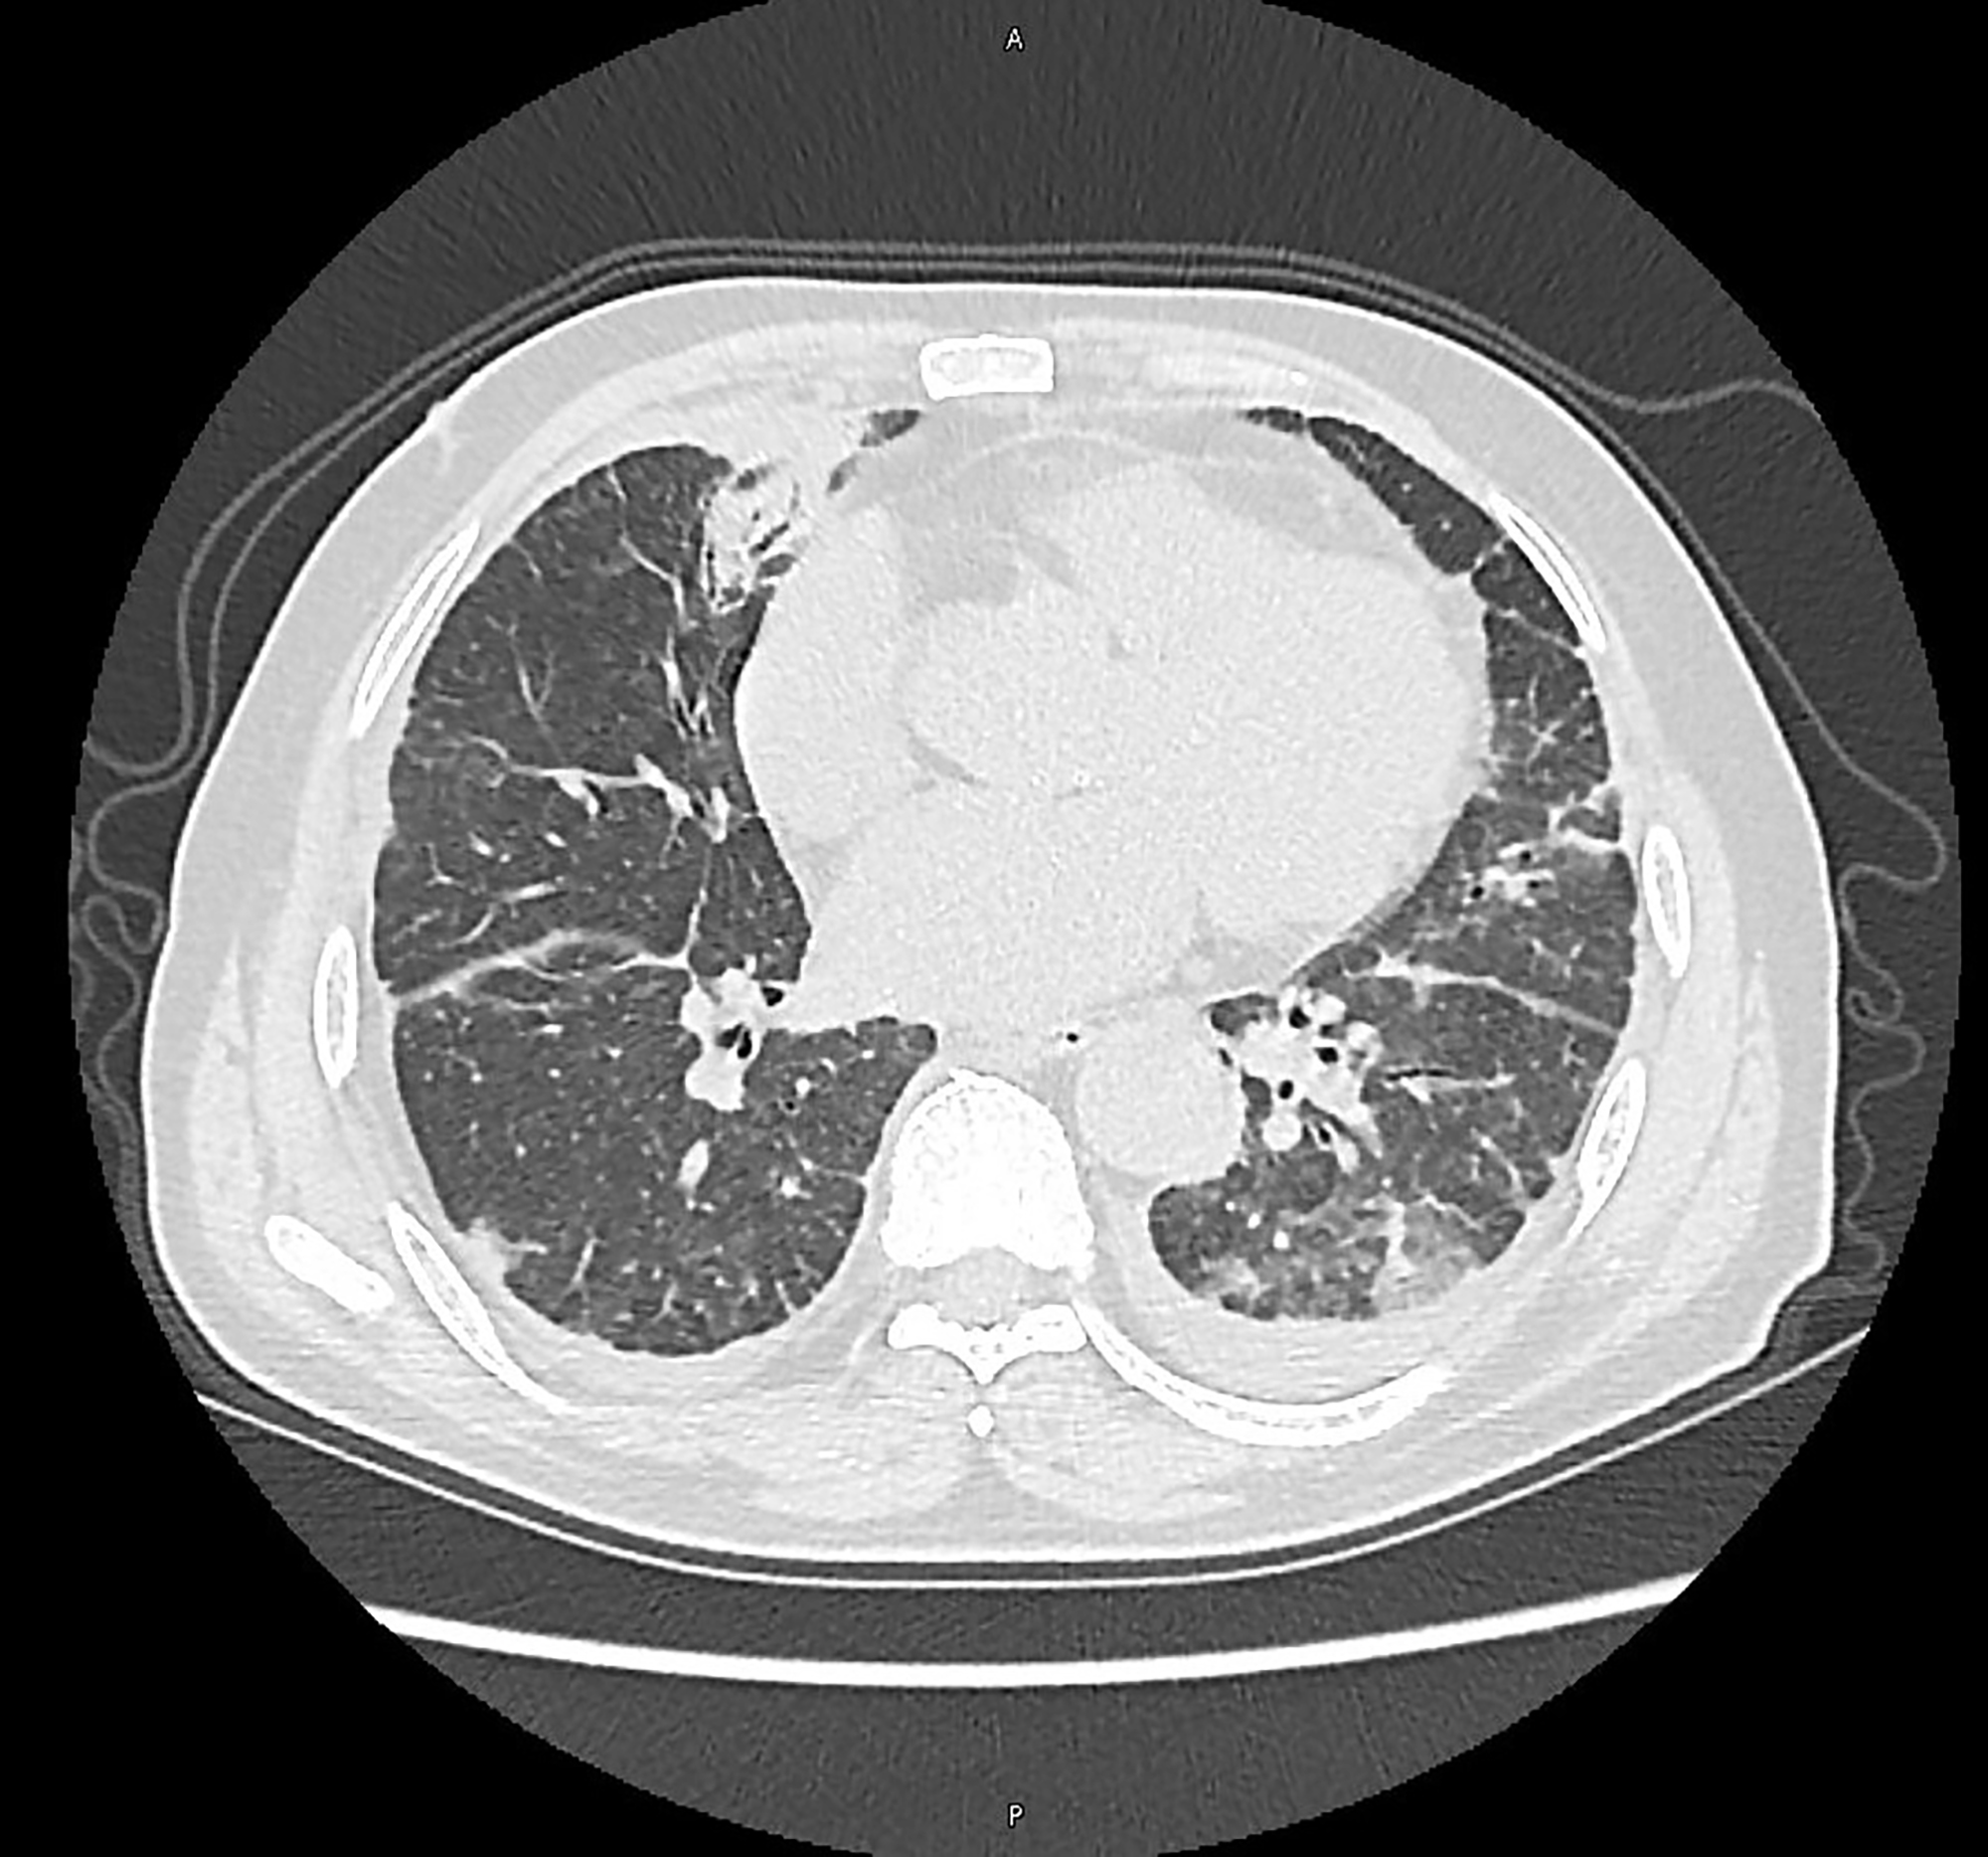

PO:22:038 | Recurrent Pneumonias and Persistent Inflammation in VEXAS Syndrome: The Role of BAL in Differential Diagnosis

Francesco Ghellere1, Bernardo D'Onofrio1, Maria Chiara Ditto1, Salvatore Panaro1, Francesca Piccione1|2, Giacomo Tanti1, Enrico Fusaro1, Simone Parisi1 | 1SC Reumatologia, Città della Salute e della Scienza Torino, Italy; 2Fondazione Ricerca Molinette Torino, Italy